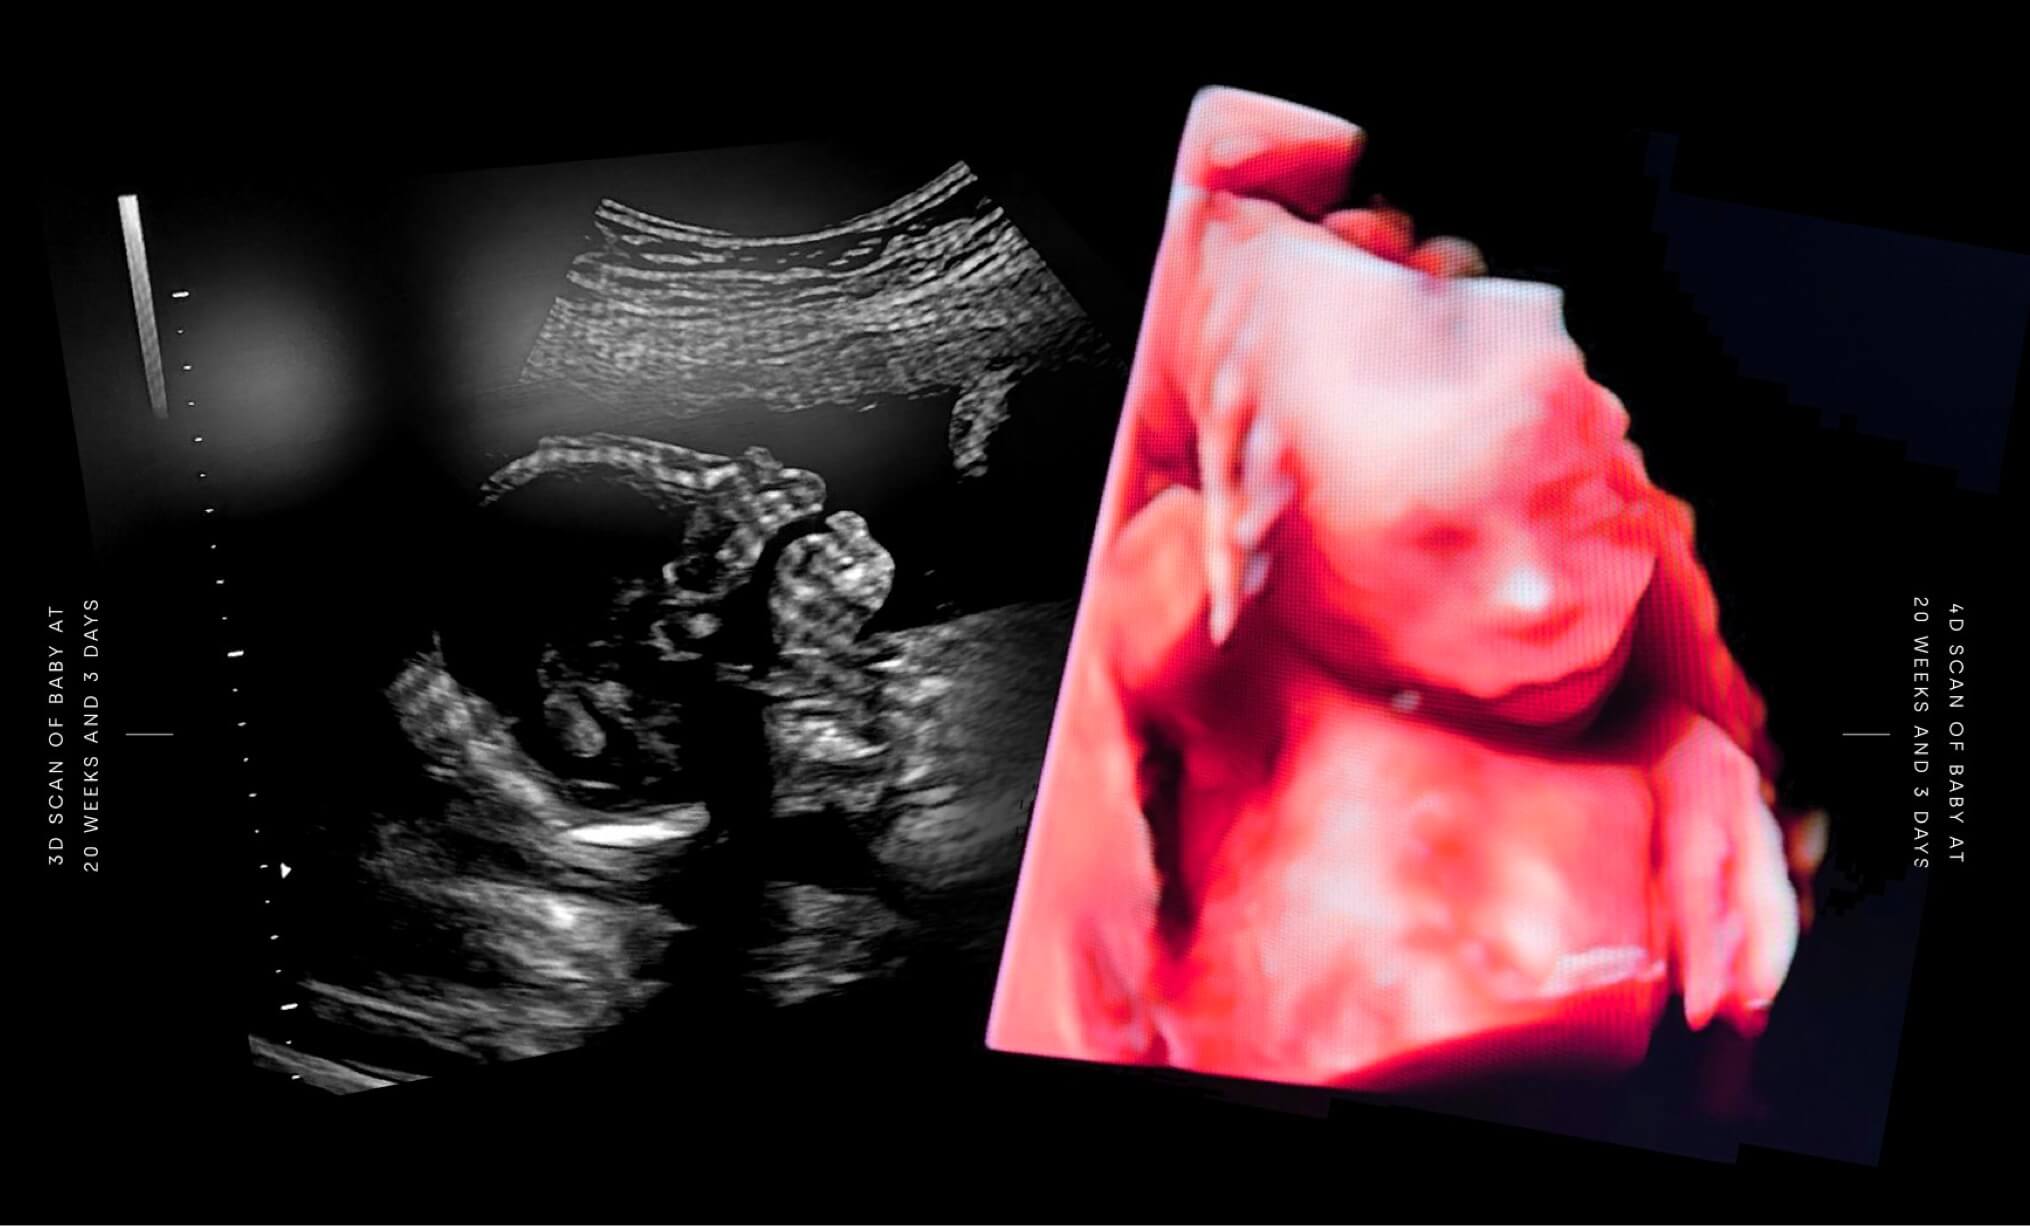

Our increasing understanding of life before birth shows the humanity of the unborn child and its development through all nine months of pregnancy.

All development milestones are sourced from the NHS pregnancy week-by-week resource. Unless otherwise captioned, images for each milestone are an artist’s render based on 3D models of the unborn child.

By 24 weeks gestation, the current gestational limit for abortion, the baby has already been fully formed for 12 weeks. Please note: The ages referenced below are gestational ages dated from the first day of the mother’s last menstrual period (LMP). The abortion limit of 24 weeks in England and Wales is measured by gestational age.

Pictures of the same baby from south London at 12 weeks 3 days; 20 weeks 3 days; and birth (41 weeks 4 days)